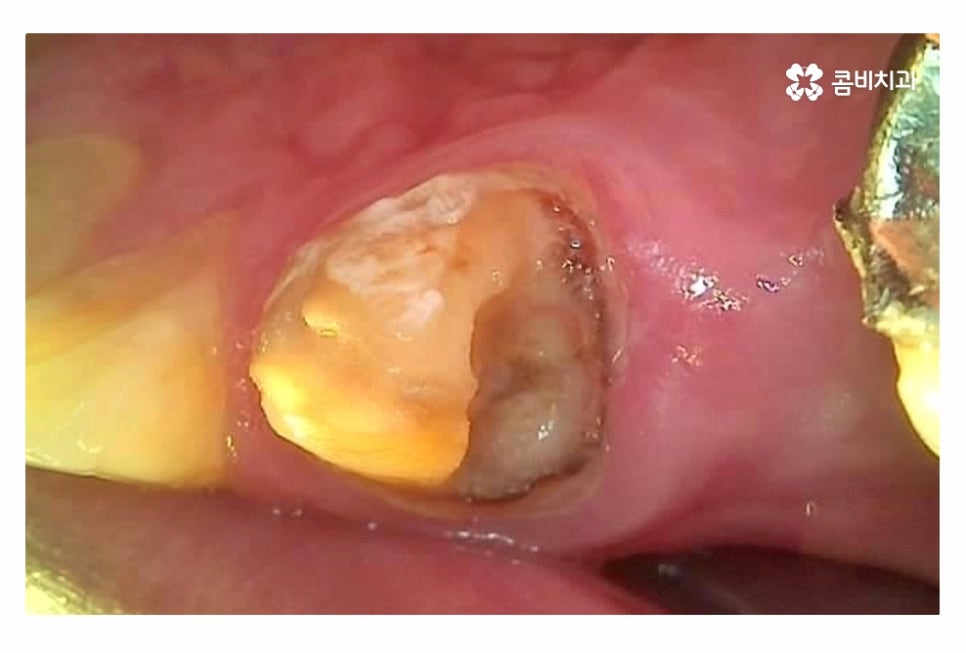

충치로 인해 치아를 잃게 되는 대표적인 사례라면

이미 과거에 치료를 했거나 치아 사이처럼 눈에 잘 띄지 않는 부위에

충치가 심해져서 치수 혹은 치아의 뿌리까지 손상이 심해진 경우라고 할 수 있어요.

충치는 누구나 발생할 수 있고 과거에 레진이나 인레이 등의 치료를

했던 분들이라면 시간이 지날수록 주변 치아 혹은 치료에 쓰인 재료가

손상, 마모 등을 거치게 되는데 치아 속에 2차 충치가 발생하는 경우에는

그로 인한 치아 손상이 심각한 상황으로 커지는 경우가 많다고 할 수 있어요.